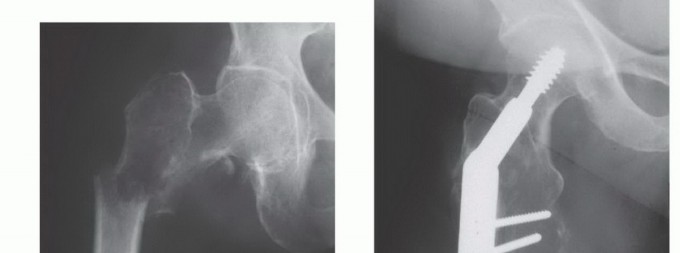

الشكل 1: أ. صورة أشعة سينية تظهر ورمًا نقيليًا في الحُق الأيمن لدى رجل يبلغ من العمر 72 عامًا ولديه تاريخ معروف بسرطان الغدة الدرقية. ب. يظهر التصوير المقطعي المحوسب (CT) تدميرًا واسعًا للعظام وامتدادًا للأنسجة الرخوة. محاولة الاستئصال بناءً على النتائج الشعاعية وحدها قد تؤدي إلى استئصال جزئي للآفة ونزيف محتمل بسبب الأوعية الدموية الكثيفة لهذا الورم. بالنظر إلى هذه النتائج الشعاعية، خضع هذا المريض لانسداد وعائي قبل الجراحة مما قلل من فقدان الدم أثناء الجراحة وسمح باستئصال ناجح.